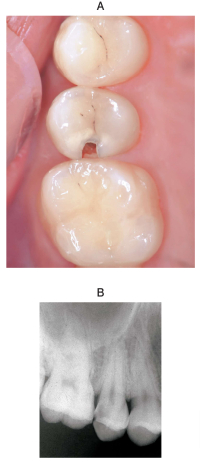

20 歳の男性。上顎右側第二小臼歯の一過性の冷水痛を主訴として来院した。6か月前から気付いていたが、強い痛みがないためそのままにしていたという。他に症状はない。プロービングデプスは全周2mm であった。象牙質齲蝕と診断し齲蝕除去を行うこととした。初診時の口腔内写真とエックス線画像を別に示す。

処置に際し必要なのはどれか。3つ選べ。

a. 齲蝕検知液塗布

b. ラバーダム防湿

c. ウッドウェッジ挿入

d. セクショナルマトリックス装着

e. Ivory のシンプルセパレーター装着